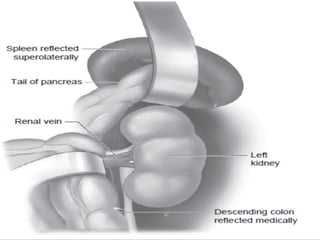

RCC WITH IPSILATERAL ADRENALRCC WITH IPSILATERAL ADRENAL

INVOLVEMENTINVOLVEMENT

 DespiteDespite poor cancer specific outcomespoor cancer specific outcomes associatedassociated

with ipsilateral adrenal involvement by RCC, a smallwith ipsilateral adrenal involvement by RCC, a small

but significant proportion of patients can expect abut significant proportion of patients can expect a

durable cure following complete surgical resection.durable cure following complete surgical resection.

 As such, patients with preoperative orAs such, patients with preoperative or

intraoperative evidence of adrenal involvement, asintraoperative evidence of adrenal involvement, as

well as patients with features of LARCC shouldwell as patients with features of LARCC should

undergo nephrectomy with concomitant en blocundergo nephrectomy with concomitant en bloc

adrenalectomyadrenalectomy..